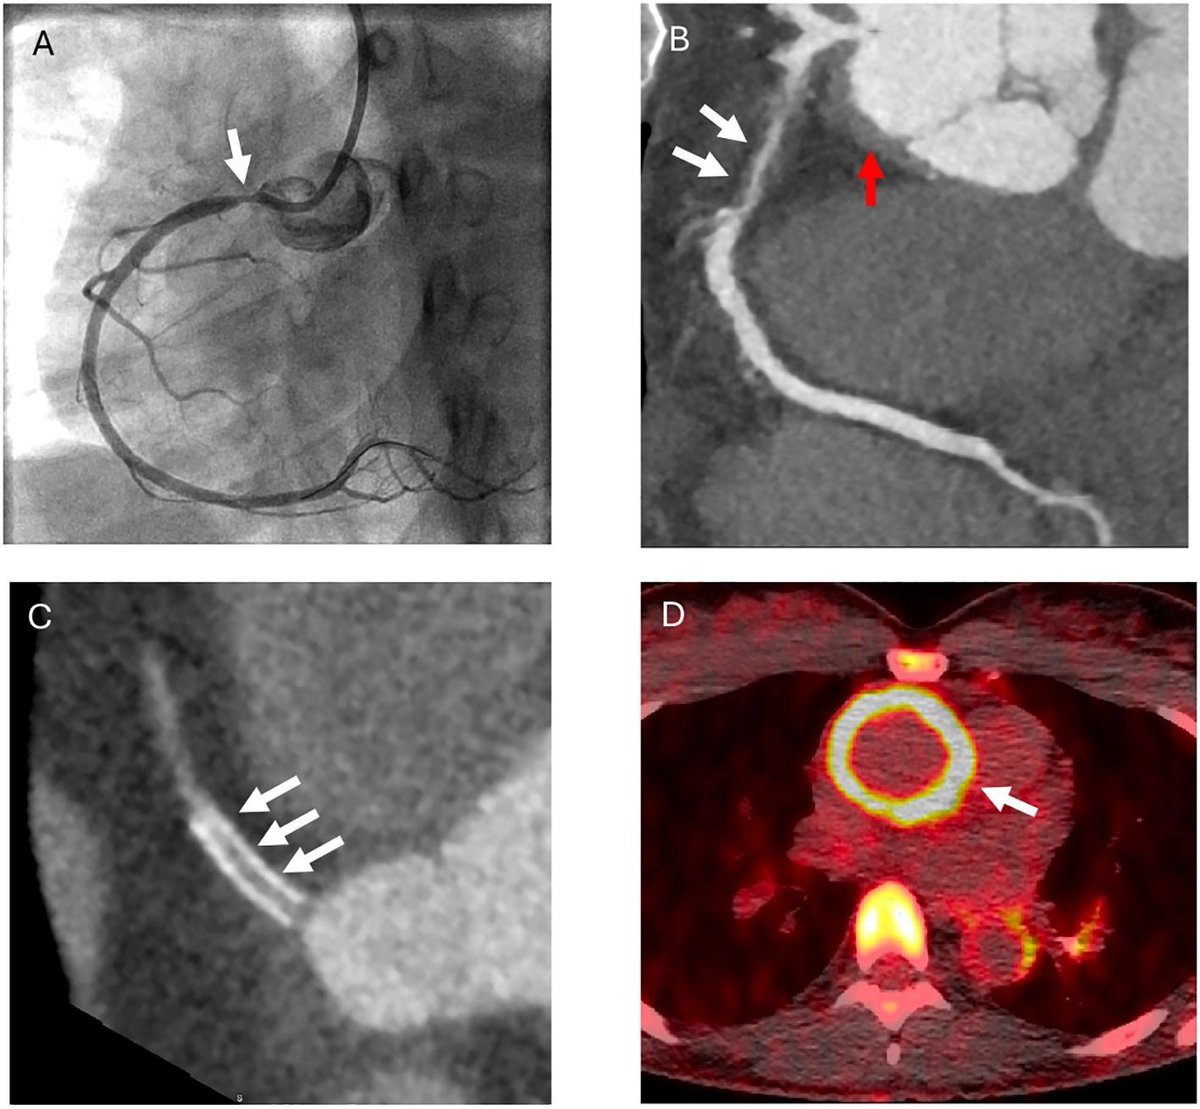

Hydralazine and the Rare Risk of Vasculitis

Since the 1980s, hydralazine has been a notable cause of drug-induced lupus, and inferred to cause vasculitis as well. A retrospective cohort study from Canada has shown that vasculitis resulting from hydralazine is possible, but rare.